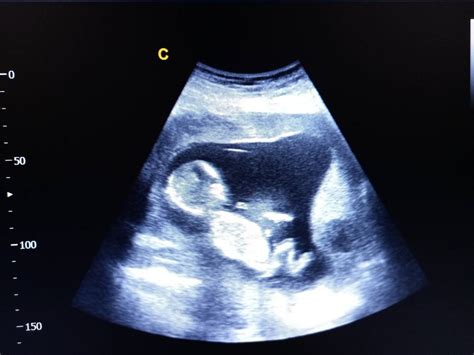

Săptămâna 6 este marcată de ecografia de confirmare, unde vei putea auzi, probabil, pentru prima dată inima bebelușului. Embrionul are un aspect curbat, cu mici umflături pentru brațe și picioare, și muguri pentru ochi și urechi. Pot apărea primele simptome de sarcină, precum sensibilitatea la mirosuri sau sâni mai plini.